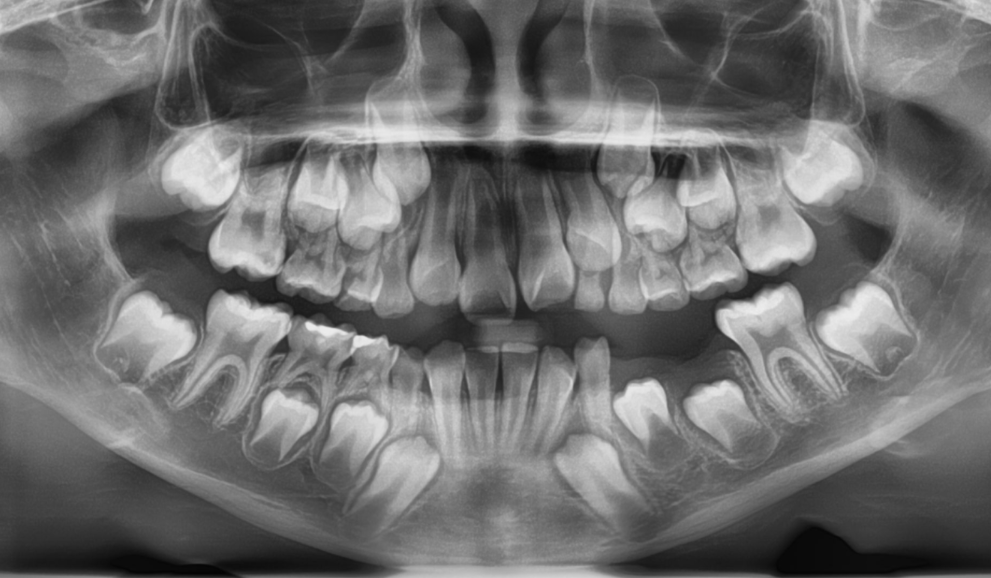

Tratamiento ortodóntico temprano (a partir de los 7 años)

Las evaluaciones tempranas nos ayudan a detectar posibles problemas antes de que se conviertan en algo mayor. Guiamos el crecimiento de la mandíbula, creamos espacio para los dientes que van a erupcionar y sentamos las bases para una sonrisa hermosa y saludable.

X-ray image of a child's teeth showing both primary and developing permanent teeth.

Seguimiento y control

Las visitas regulares de seguimiento y monitoreo permiten a la ortodoncista evaluar el crecimiento de la mandíbula, la erupción de los dientes y el desarrollo de la mordida, para iniciar el tratamiento en el momento más efectivo. Este enfoque preventivo ayuda a evitar que los problemas empeoren y puede acortar o simplificar el tratamiento futuro. Contar con una especialista supervisando estas visitas garantiza una evaluación experta, una detección temprana y un plan personalizado adaptado al desarrollo único de tu hijo o hija.